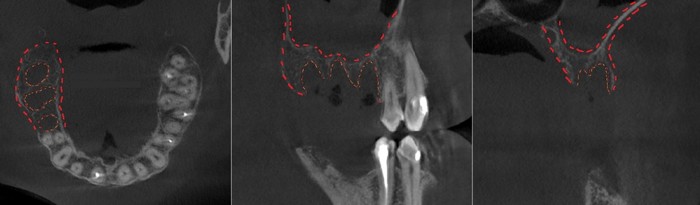

Согласитесь, не особо эстетично. Ортопантомограмма:

Фрагмент компьютерной томографии (вид сбоку):